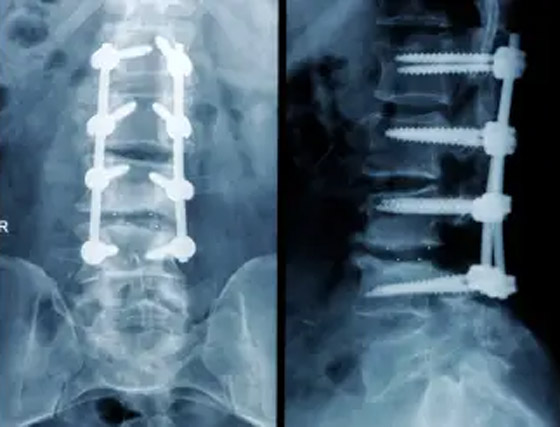

وفي حالة شارون سميث، استخدم ويليامسون مسامير أطول من اللازم في عمودها الفقري. وعُثر على أحدها بالقرب من الشريان الأورطي، وكان الآخر يلامس شرياناً منفصلاً. ولو انقطع، مثلما حدث لأوكونور، لكانت ماتت في ظرف ساعتين. وعاشت شارون مع المسامير لمدة عامين قبل أن يخضعها ويليامسون لعملية لإزالة أحدها، لكن الضرر الذي لحق بأنسجتها وأعصابها كان قد حدث بالفعل وهي تعيش عواقبه من حينها. وتقول: "انتهى بي الحال إلى إجراء ثلاث عمليات جراحية كان يفترض أن تكون واحدة. ولو تمت بشكل صحيح من البداية، لكانت حياتي مختلفة تماماً. أنا غاضبة جداً".

وضع مسامير بطريقة خاطئة بظهور مرضاه! أخطاء كارثية لجراح بمستشفى بريطاني عريق صورة رقم 2